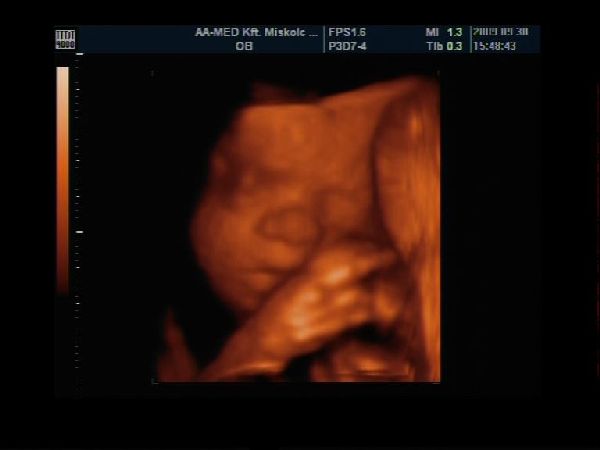

Van egy pár percem a gép előtt, gyorsan teszek fel Nektek képecskéket :wink:

Szerintem olyan szép pofija van és természetesen nekem Ő a legszebb :lol: :lol: :lol:

Szerencsére szépen mutatta magát, láttuk mindenét, most már biztos, hogy cunis :lol:

Apa is nagyon élvezte, főleg, hogy ennyire jól lehetett látni a kis tündérkénket :D

A képek 27 hetese és 1 napos: Kép Kép Kép Kép

Akella, ez egy gyönyörűség, ahogy mosolyog, meg cuclizza az ujjacskáját, olyan cuki :D . Istenem, de rég volt, hogy ilyen képeket nézegettünk UH-on. :|

Akelle naggyon gyönyörűséges a kis pinnás :lol: :lol: Olyan édes kis pofija van :D